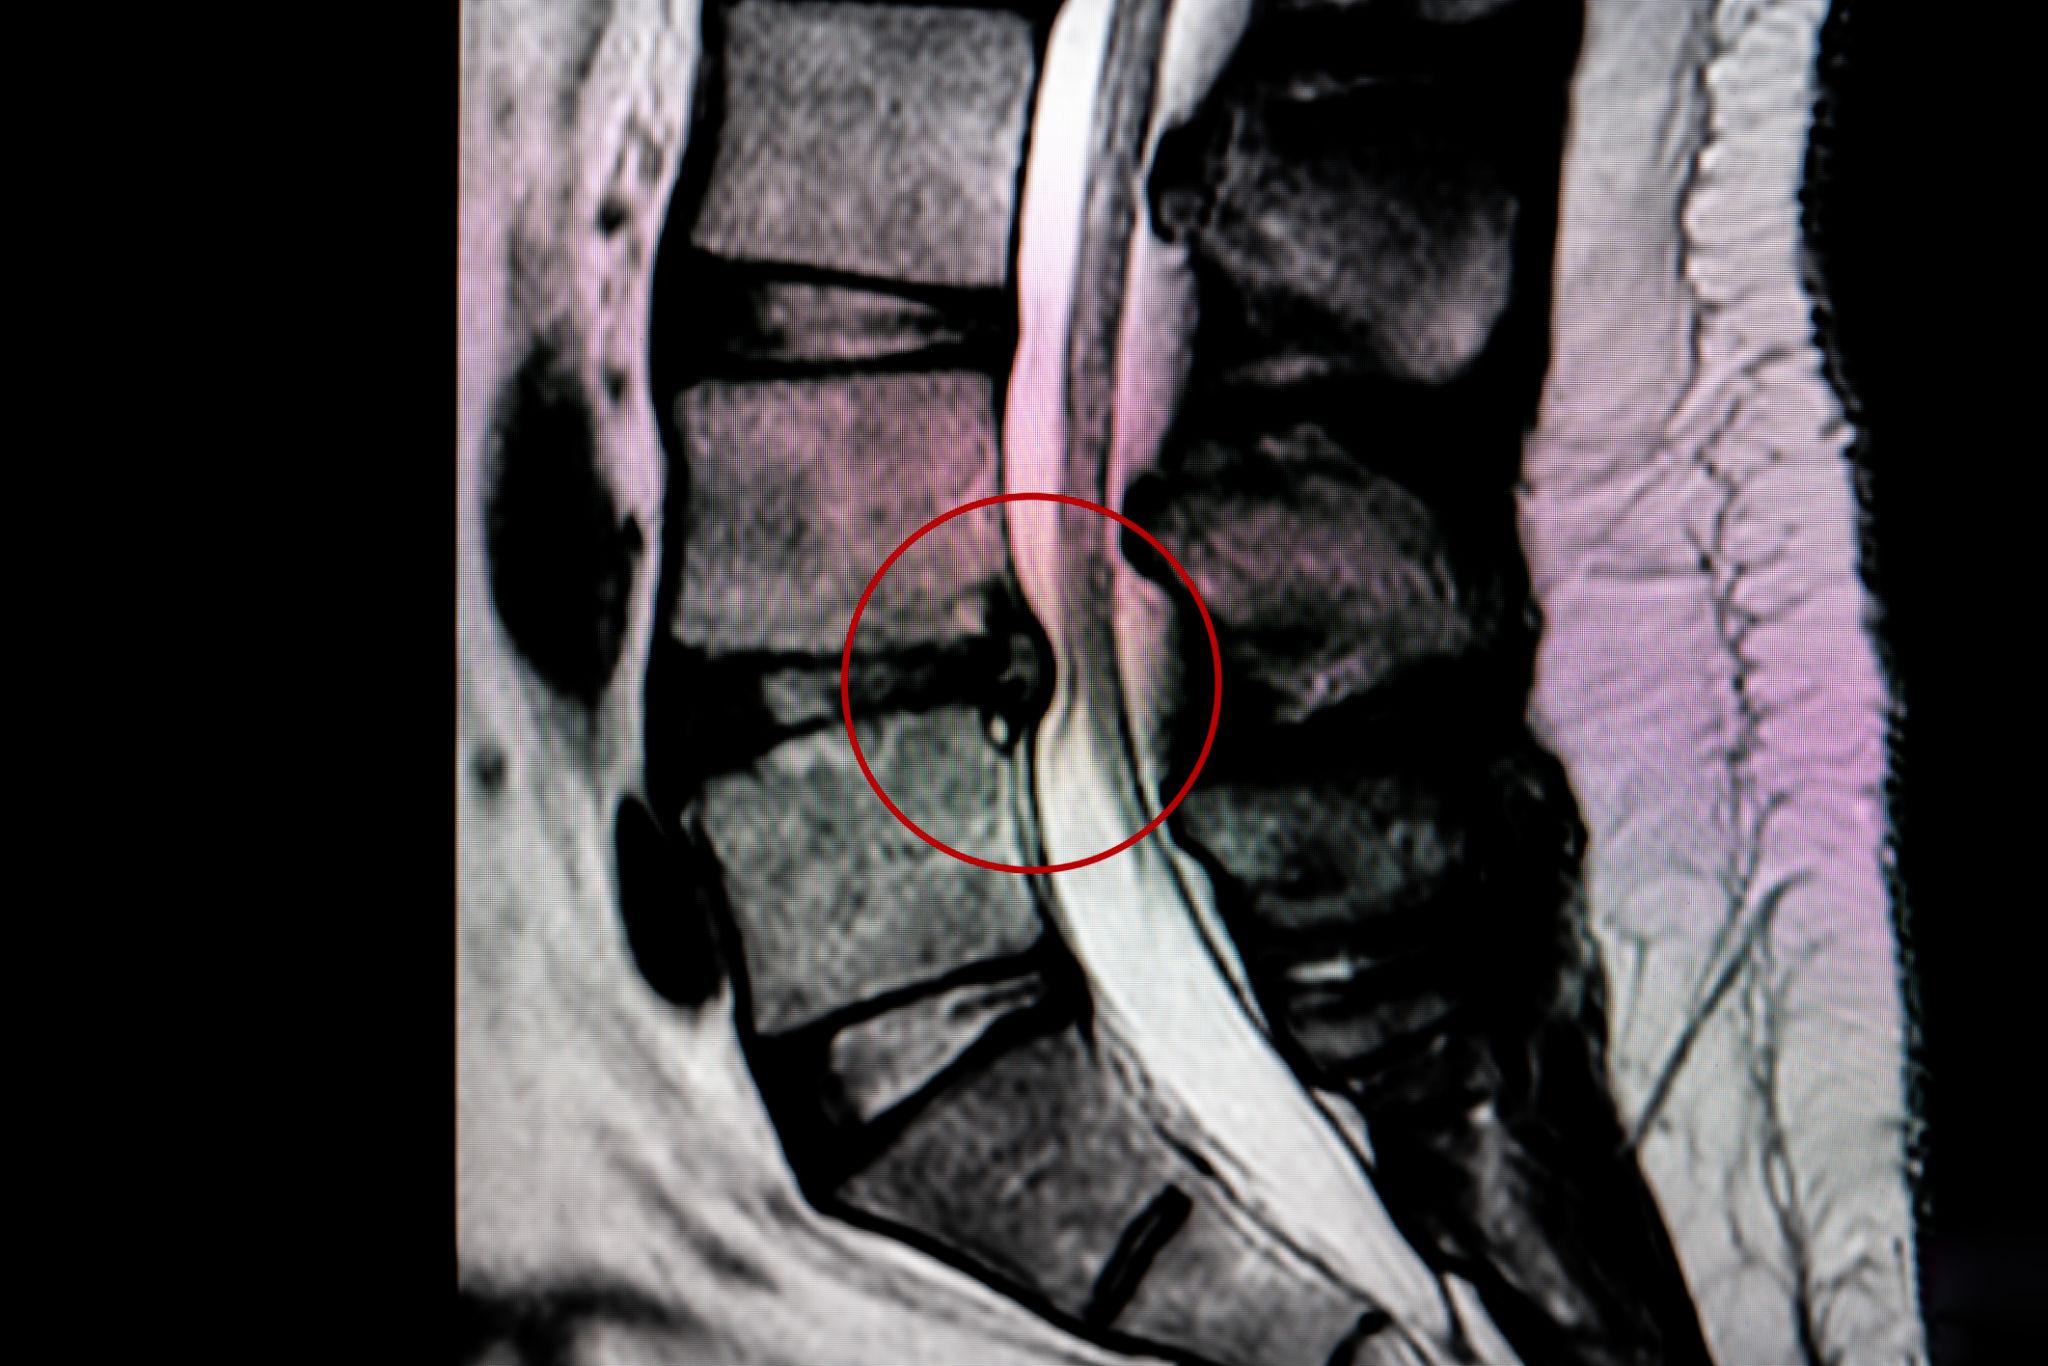

A herniated disc occurs when the inner disc material pushes through a tear in the outer disc wall. This can place pressure on spinal nerves and cause severe symptoms.

A bulging disc is an early form of disc degeneration where the disc extends outward but has not ruptured. Although often considered “less serious,” bulging discs can still irritate nerves and restrict movement.

Degenerative Disc Disease (DDD or DJD) occurs as discs lose hydration, elasticity, and height over time. This increases spinal instability and joint stress.

Osteoarthritis affects the facet joints of the spine when cartilage breaks down over time. This leads to inflammation, stiffness, and sometimes bone spur formation.